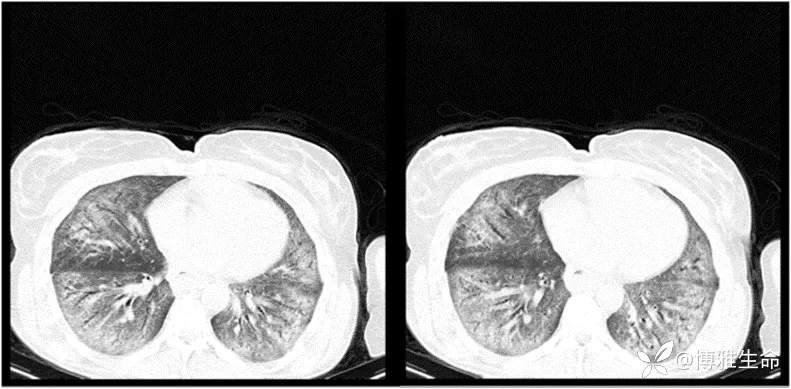

胸部CT扫描(如下图)显示弥漫性磨玻璃样实变伴胸膜下网状影和纤维化改变。此外,肺动脉主干扩张(33 mm),其他检查结果未见特殊,结合既往病史和当前病情,诊断为系统性硬化病(SSc)引起的间质性肺病(ILD)。

图片来自文献[1]